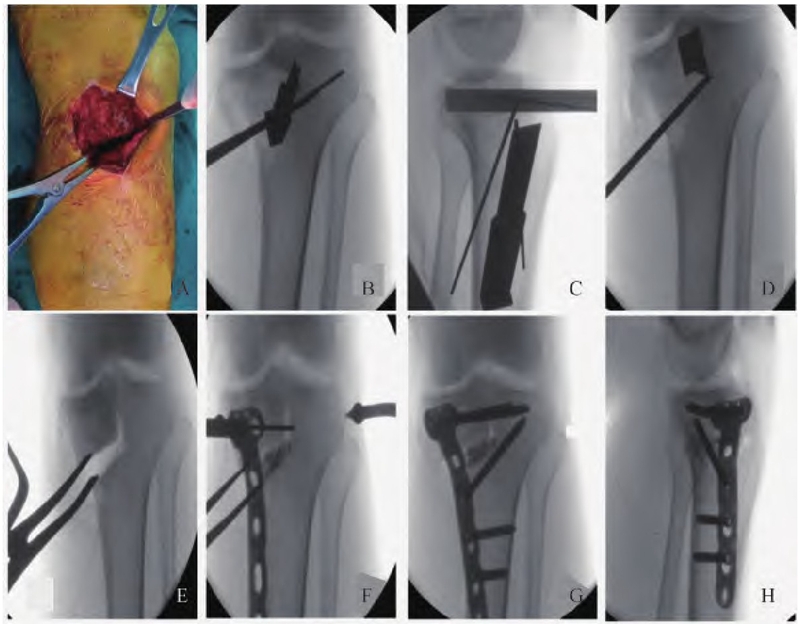

关节内探查清理结束后退出镜头,取胫骨内侧中心点经自关节远端1cm处向胫骨结节下缘方向做长约5~7cm切口(图3A),依次切开皮肤、皮下组织、深筋膜,钝性分离,暴露胫骨近端前内侧,松解部分鹅足肌腱,适当剥离内侧副韧带远侧止点,利用电刀在骨面作“L”型截骨线标记,横向截骨线为自平台下4cm斜向腓骨头方向,纵向截骨线自胫骨外侧髁间隆起尖端向远处延伸(一般位于髌韧带内缘),两线交点为“L”型截骨线顶点。透视下插入2.0mm克氏针,横向克氏针方向与OWHTO技术相同(自内侧截骨线向上胫腓联合方向平行插入两枚),纵向克氏针自截骨线垂直向后插入,注意纵向克氏针无需穿透后侧皮质骨。用带有刻度的薄骨刀沿克氏针方向敲入截骨,截骨时尽量维持屈膝位,避免神经血管损伤。纵向截骨尽量保留胫骨近端0.5cm的距离,作为截骨绞链(图3 B-D)。截骨完成后进行撑开,内侧的撑开器放置应偏后,避免平台后倾的情况发生。撑开角度可根据术前的设计或术中力线杆透视,以及内外侧平台面线夹角决定。透视确认截骨角度至目标角度(图3 E),于胫骨前内侧插入T型钢板,置入螺钉,于截骨处填塞羟基磷灰石人工骨(图3 F)。C臂机再次透视确认胫骨内侧平台高度恢复良好及内固定装置位置良好(图3 G-H)。冲洗术口,逐层缝合切口并包扎。

图3 TCVO术中截骨情况